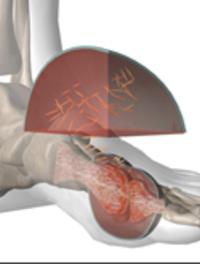

L’aponévrosite plantaire est l’une des plaintes somatiques les plus fréquentes et, de ce fait, un motif majeur de consultation en pratique [...]